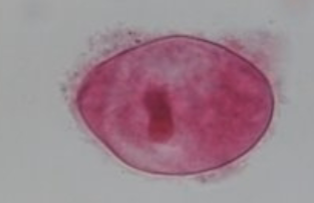

Entamoeba histolytica

MOT: Fecal / Oral (ingestion of cyst)

Infective stage: Cyst

Hosts: Human

Parts to look for: small bullseye nucleus & central karyosome